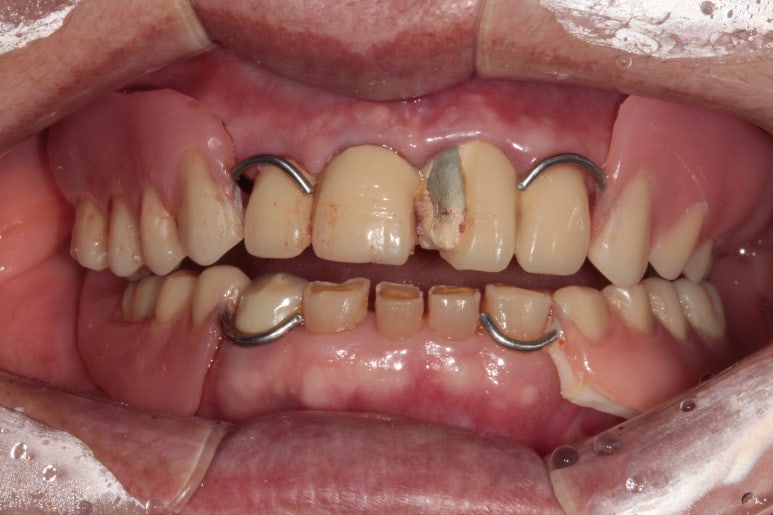

임시틀니의 착용 후 구내 사진은 위와 같습니다.

솔직히 예쁘지 않습니다... 기능도 훌륭하지 않아요...

'임시'틀니는 정말 '임시'일 뿐입니다. 식사 하실때도 잘 빠지고... 많은 환자분이 힘들어하시죠....

그래도 임시틀니의 역할은 앞에서 보았을 때 치아가 있어 보이게 해줄 수 있다는 것. (고리가 보이긴 하지만)

그리고 아래턱의 위치를 찾아가는 재활치료의 역할도 해줄 수 있다는 것을 기억해주세요.!!